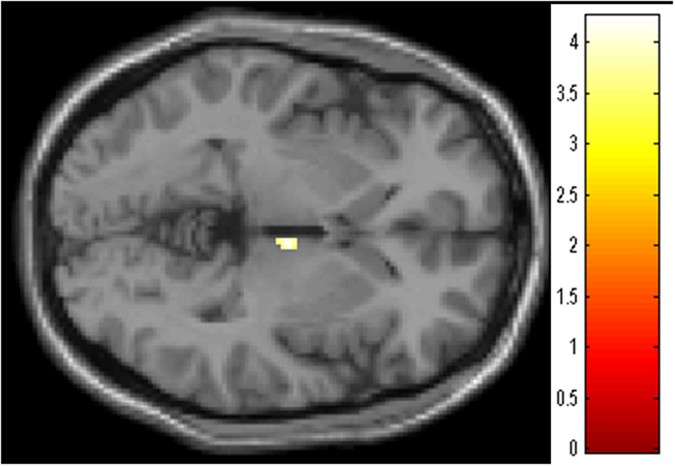

We found a significant group x time interaction in the rGMV in the right thalamus (x = 6, y = −12, z = −2; p < 0.05, svc, Fig. 2). The estimated values of the right thalamic volumes were significantly increased in the Wo group (Wo: 0.254 ± 0.022 to 0.263 ± 0.023, p < 0.05, paired t-test), but not in the Ho group (0.245 ± 0.019 to 0.237 ± 0.029, p = 0.13, paired t-test).

Regions showing significant group (Ho/Wo) × time (Post/Follow-up) interactions (right thalamus; x = 6, y = −12, z = −2; p < 0.05, svc).

The colored bar shows the scale of the t-value. Abbreviations: Rt, right; Ho, hormonal therapy; Wo, without adjuvant therapy; Post, shortly after surgery; Follow-up, 6 months after surgery; svc, small volume correction.